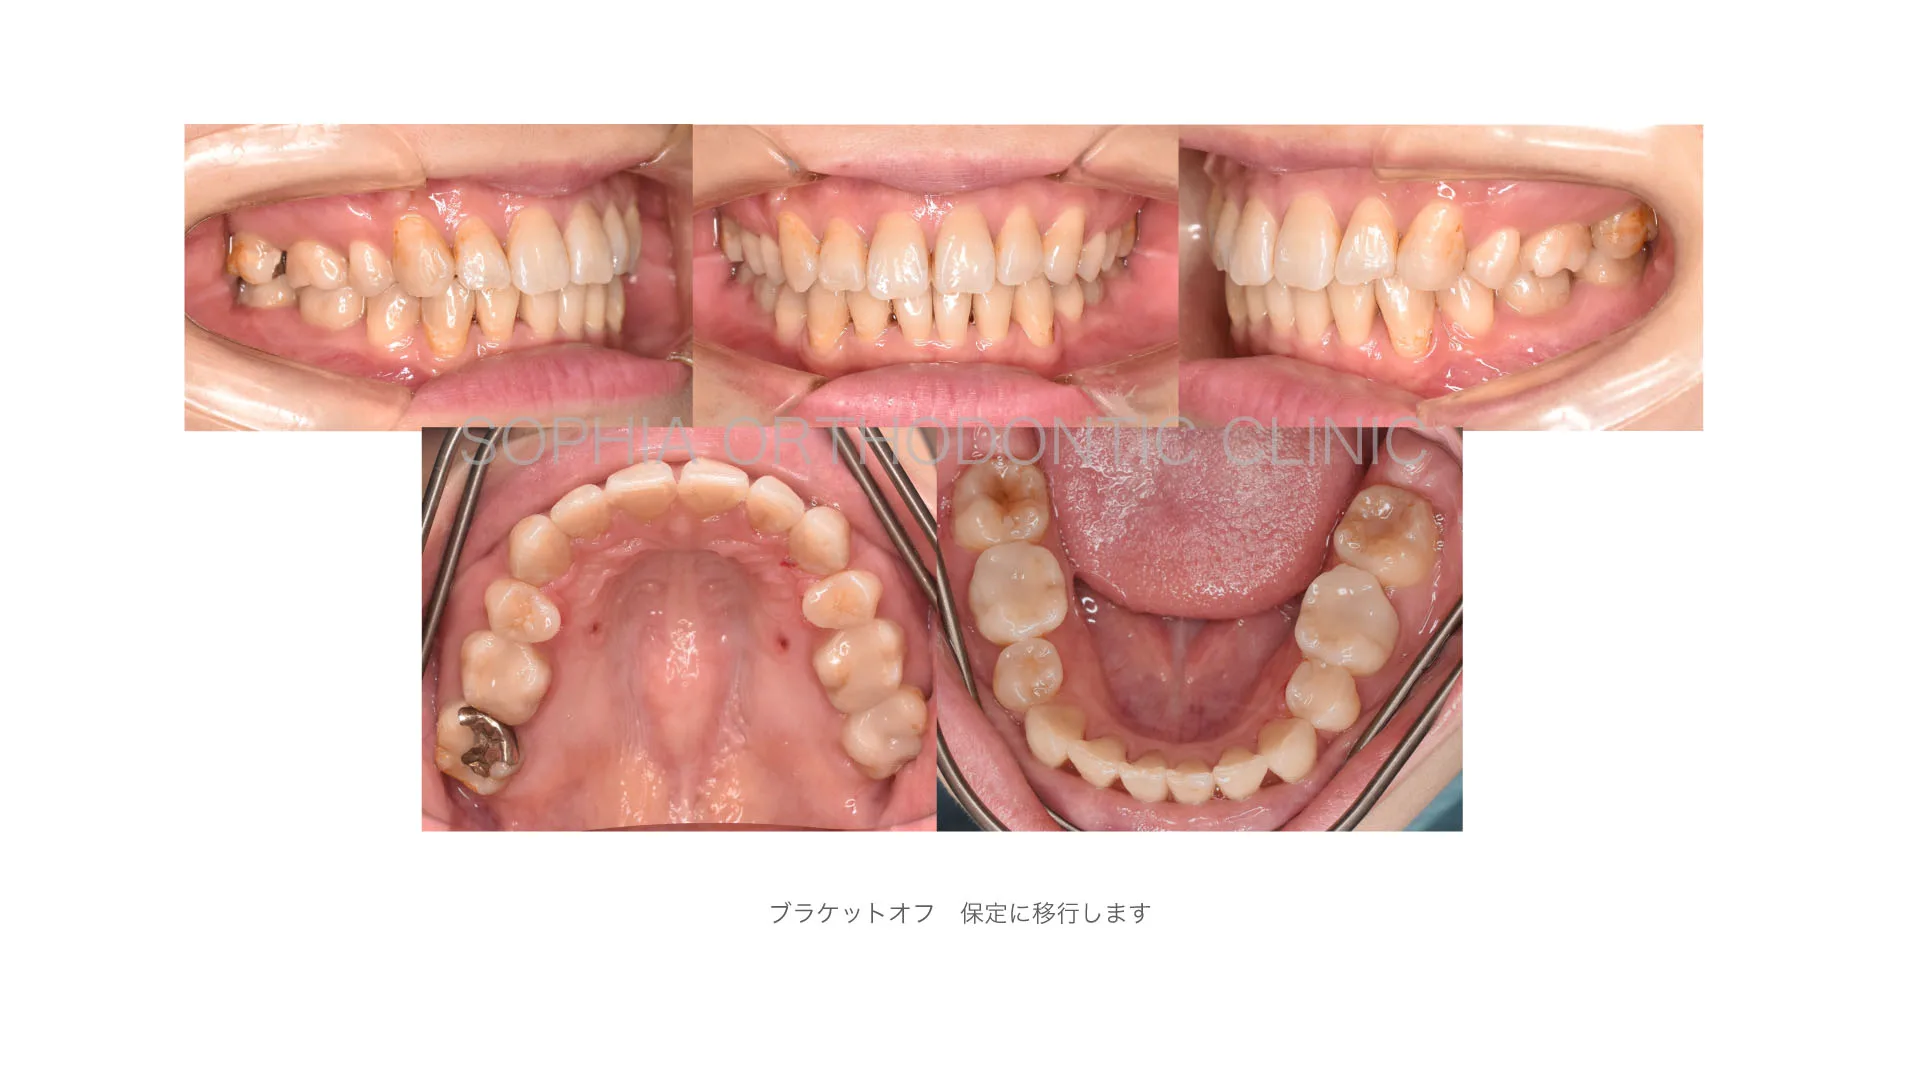

症例 前突